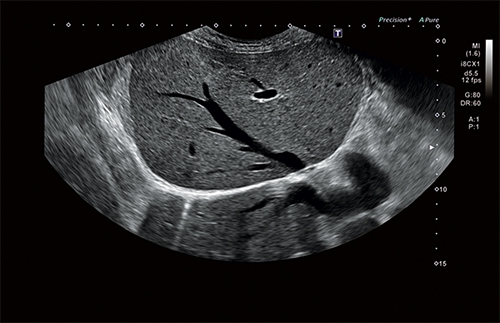

Ультразвуковая система Aplio i700 обеспечивает лучшее качество диагностики за максимально короткое время. Сочетая превосходное качество изображений с исключительной простотой использования и большим выбором программных и аппаратных опций, модель i-серии Aplio 700 является универсальным ультразвуковым прибором.

Универсальная УЗИ система «Кэнон Тошиба Аплио i700» премиального класса может похвастаться новейшими технологическими решениями, множеством современных режимов и программным обеспечением высшего порядка. Все это позволяет достичь поистине невероятного качества сканирования, визуализации и детализации. Этот многофункциональный сканер нового поколения создан для решения самых сложных задач в обширном спектре направлений медицинской деятельности.

• Режим Luminance для получения качественного изображения плода в первом триместре с помощью трехмерной реконструкции